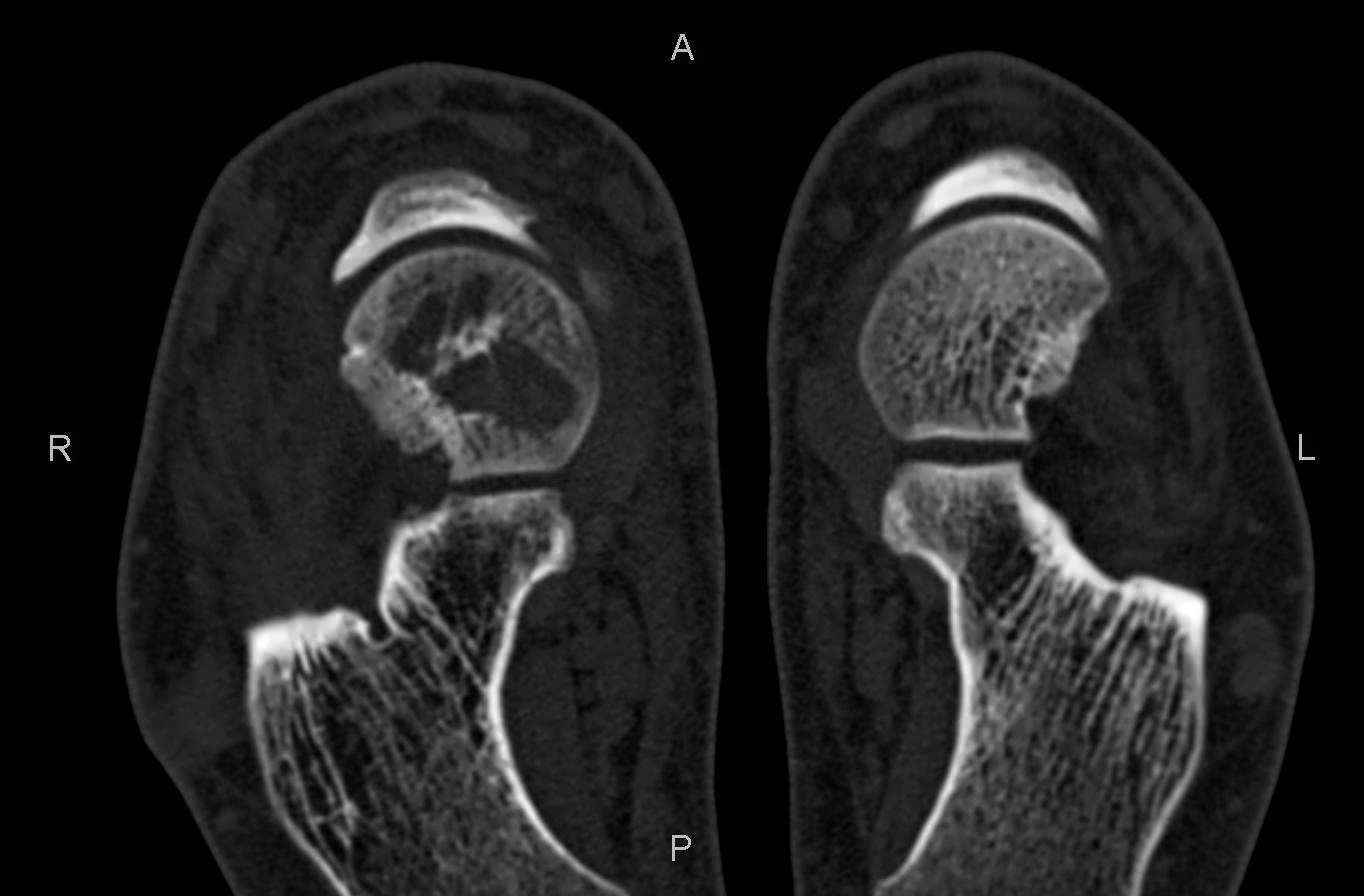

Уважаемые коллеги, обратился за помощью пациент, мужчина, 25 лет. С жалобами на болевой

синдром в области голеностопного сустава и среднем отделе стопы. Травму отрицает. Со слов,

болевой синдром в течении 1 года. Последние 1-1.5 мес периодически вынужден пользоваться

костылями. После ограничения нагрузки боли уменьшаются. Соматически здоров. До появления

болей активно занимался рукопашным боем.

На СКТ картина рассекающего остеохондрита блока

таранной кости, киста шейки таранной кости с признаками импрессии суставной поверхности. А

также - разрастания переднего края б\берцовой кости сопровождающиеся клиникой импиджмент

синдрома.